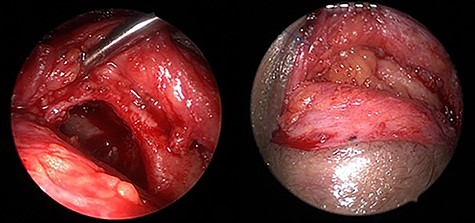

Endoscopic transorbital view of the isolated left frontal sinus cavity after completely peeling off the frontal sinus mucosa (a) and after fat obliteration of the cavity (b).